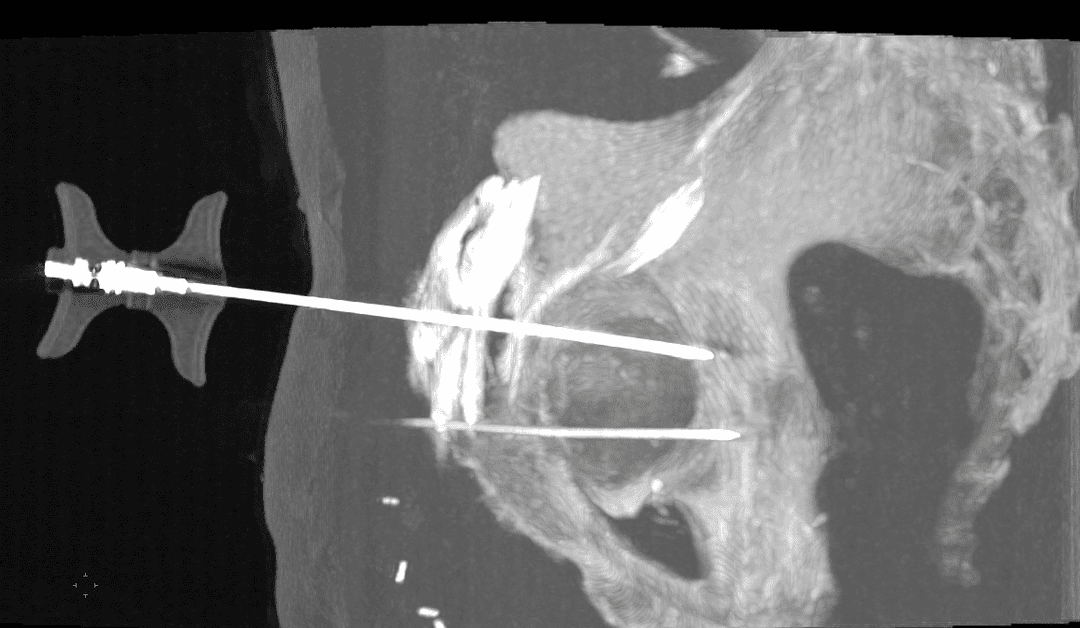

Sous anesthésie locale (parfois combinée à une légère sédation), une aiguille de guidage est introduite en se servant de la fluoroscopie pour vérifier en continu sa progression.

Insertion et déploiement du matériel d’ostéosynthèse :

Une fois l’aiguille positionnée, le vissage est réalisé en respectant la trajectoire prédéfinie, permettant de réaligner les fragments osseux.

Le vissage est ensuite fixé de manière à assurer une stabilité mécanique suffisante pour supporter les contraintes de la zone cotyloïdienne.

Contrôle post-procédural :

Un contrôle scanner final permet de vérifier la position du vissage et la qualité de la réduction anatomique, garantissant ainsi le succès de l’intervention.